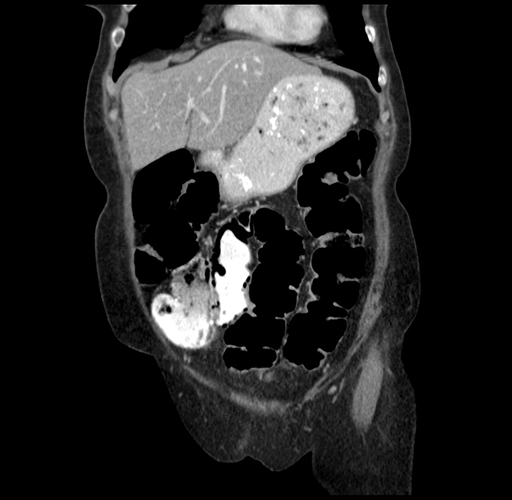

Pre-Chemo: Axial Venous

Pre-Chemo: Coronal Venous